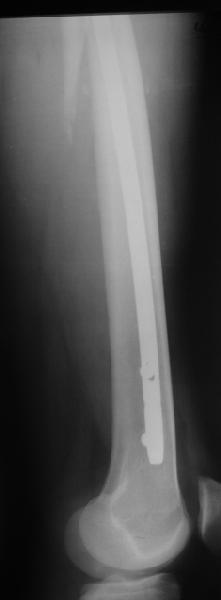

Реконструкционный гвоздь.

Да, сейчас это и у нас самый напрашивающийся выбор. Сделали гвоздем ChM, картинки в приложении.

У молодых реконструкционный гвоздь самое то. При остеопорозе надо что-то помассивнее.